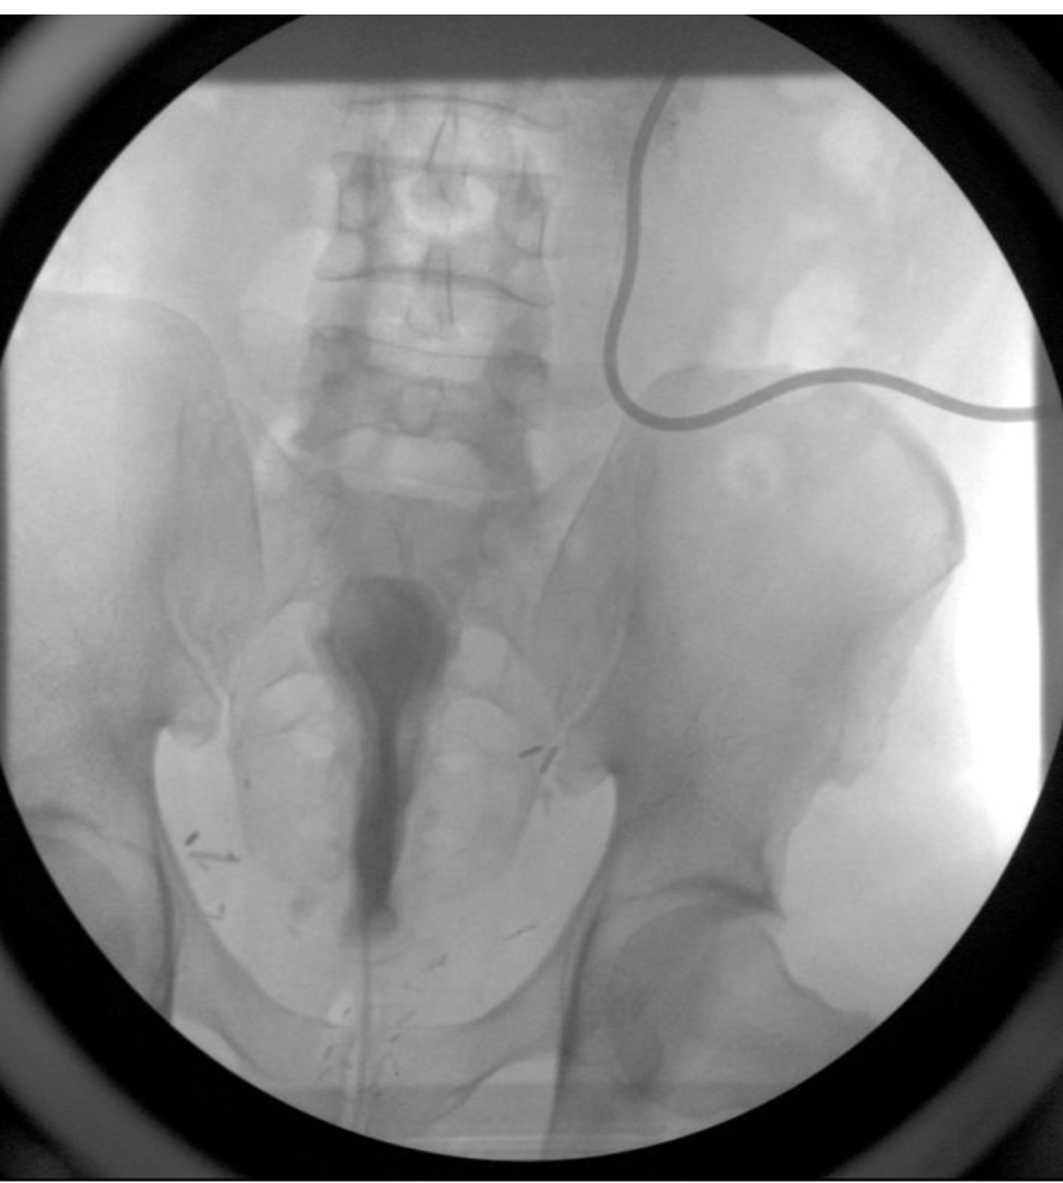

A 54-year-old African American male, presented to our facility with a prostate specific antigen (PSA) of 5.8 ng/mL. Prostate biopsy revealed three cores of Gleason 6 adenocarcinoma. On digital rectal examination he was found to have an approximately 60 g prostate, which was firm and smooth. He underwent an open retropubic radical prostatectomy (RRP). The pathologic specimen showed Gleason 7 adenocarcinoma occupying 20% of the specimen. The stage was T1cN0M0. On the fourth post-operative day, the patient presented to the Emergency Department in another facility complaining of chest pain and shortness of breath. A clinical diagnosis of pulmonary embolism (PE) was made and he was treated with a full dose of IV heparin. He subsequently developed hematuria and complained of lower abdominal pain. On physical exam, he was found to be pale, with diffuse abdominal tenderness, guarding and tachycardia. The patient was then transferred to the Surgical Intensive Care Unit (SICU) at our facility. He received two units of packed red cells. A cystogram showed complete disruption of the UVA with displacement of the bladder neck in the left upper quadrant of the abdomen producing a “pie in the sky” appearance. However, there was no evidence of urinary extravasation indicating an intact bladder neck (Fig. 1, 2). A CT scan revealed a very large pelvic hematoma displacing the bladder neck towards the left upper quadrant (Fig. 3). An IVC filter was inserted to prevent migration of thrombi so that he could discontinue the use of anticoagulants. Patient was managed conservatively for 6 - 8 weeks with gentle traction, and this helped maintaining the bladder neck within the pelvis. A cystogram showed no extravasation of urine. The Foley catheter was removed. The patient voided well initially; however, he developed bladder neck contracture (BNC) after 2 weeks. He was managed with dilation of the bladder neck, but the bladder neck did not return to the pelvis. It was found to be 2 cm away from the urethra, and a “pseudo-tunnel” made of scar tissue was seen between the true bladder neck and the membranous urethra. A surgical approach was used to explore the patient and the “pseudo-tunnel” was resected. Re-anastomosis of the bladder neck with the urethra was performed. The patient has remained continent since then and voids with minimal post void residual urine. There has been no recurrence of BNC (Fig. 4, 5). He needs intra-cavernous injections to help with erections. His post-operative PSA has remained undetectable.

![]() Click for large image | Figure 3. It shows pre-operative cystogram showing cephalic displacement of the bladder neck, and compression of the bladder. |